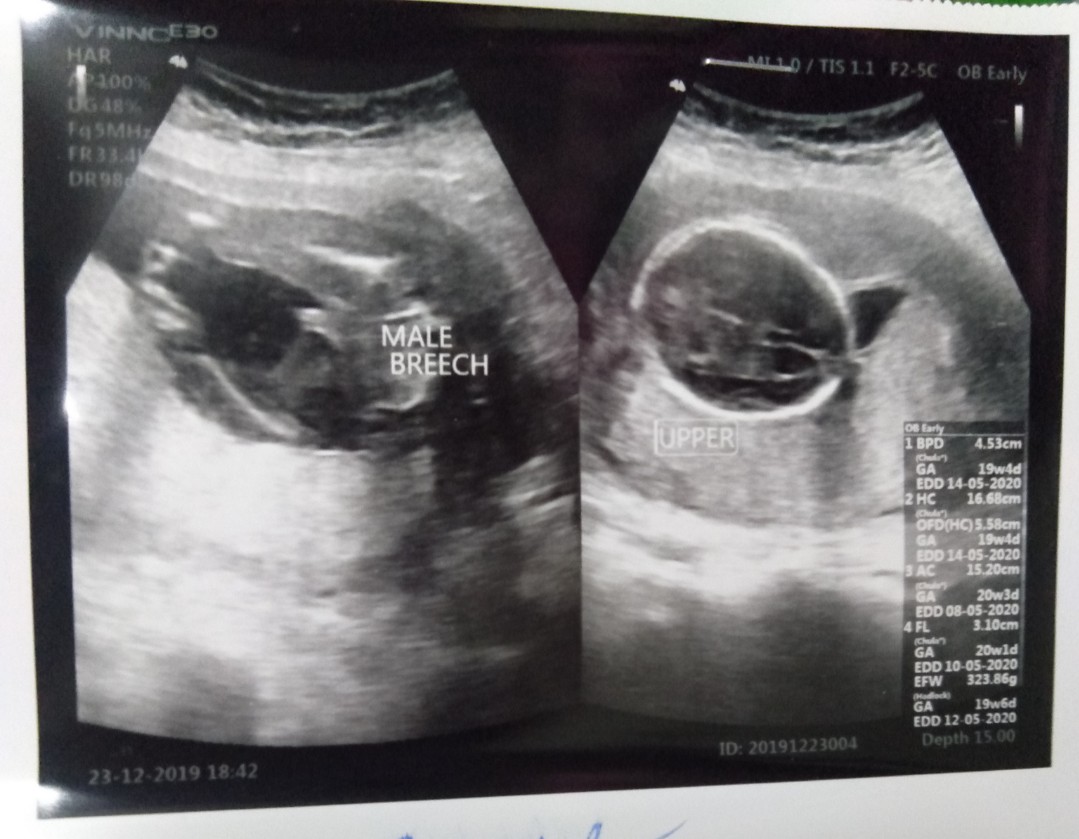

บ้านนี้คุณหมอบอกลูกชาย100%ค่ะ